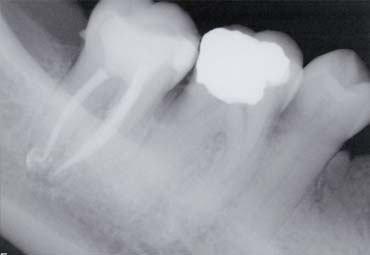

X-rays showing root canal treatment

An x-ray will need to be taken at the beginning and end of treatment to ensure that it has been carried out as well as possible.